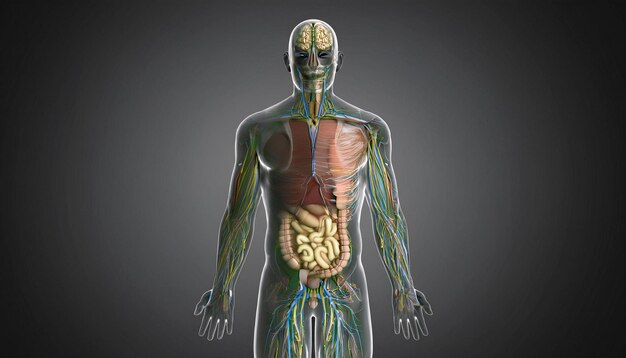

Human Anatomy Translucent Figure With Internal Org 404887999

14/11/2025

ร่างกายมนุษย์